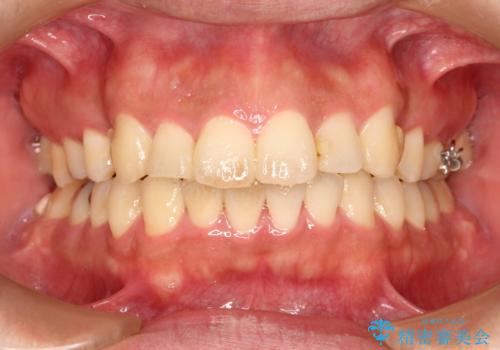

- 20代男性

- 出っ歯が気になるとのことで来院されました。

上顎の前から4番目の歯を両側、合計2本抜歯して矯正する計画としました。

目立たない装置がご希望でしたので、上下裏側ワイヤー装置を選択されました。